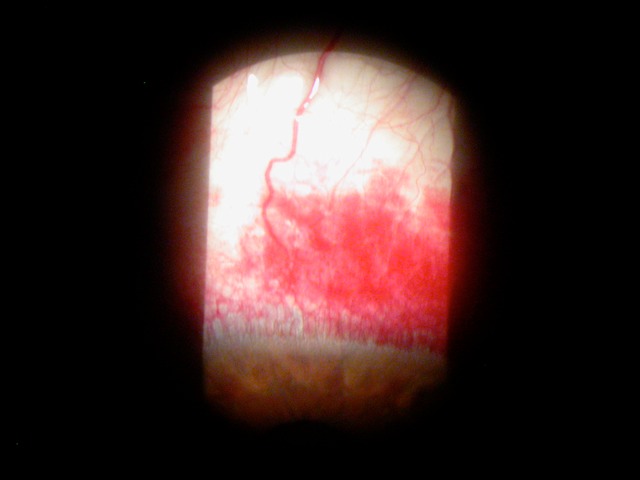

hemorrhage